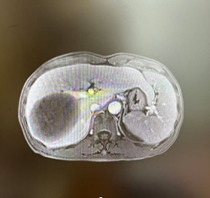

新辅助治疗前CT

由于病人一般情况较好,肝功能良好(Child-pugh A级),经多学科会诊临床确认肿瘤为IIb期肝细胞癌,属于可切除性肝癌,但存在高危复发因素,建议先行新辅助治疗后手术切除。经两次肝动脉关注化疗(HAIC)(奥沙利铂+5-Fu+亚叶酸钙方案)和两个周期的靶向免疫治疗(仑伐替尼+帕博利珠单抗方案),第二次介入造影是肿瘤血供不明显,第二次介入治疗4周后复查CT提示肿瘤缩小不明显但坏死征象明显,经MRI证实仍有少许血供,于是经多学科会诊后决定行前入路右半肝切除术。